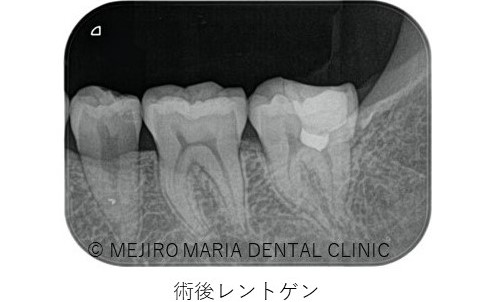

軟化象牙質(虫歯)を完全に除去した後に、歯髄を2mm程切断し、MTA(歯科用コンクリート)を充填しました。

2週間後の2回目来院時に生活歯髄反応が正常であることを確認し最終補綴に移行しました。